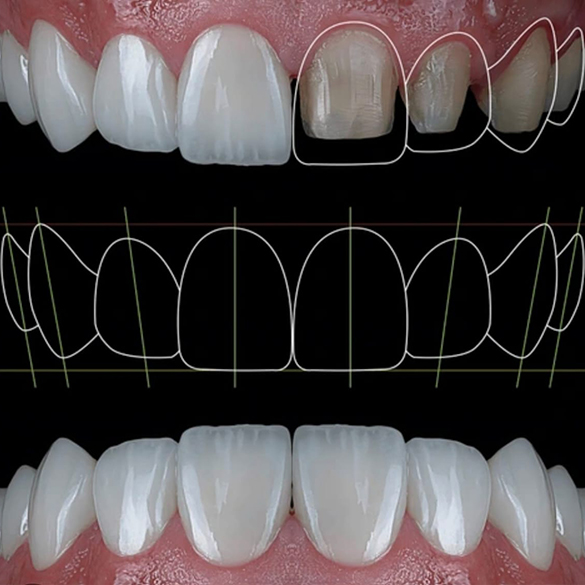

Our services and expertise

Dental treatment

Confident Smile